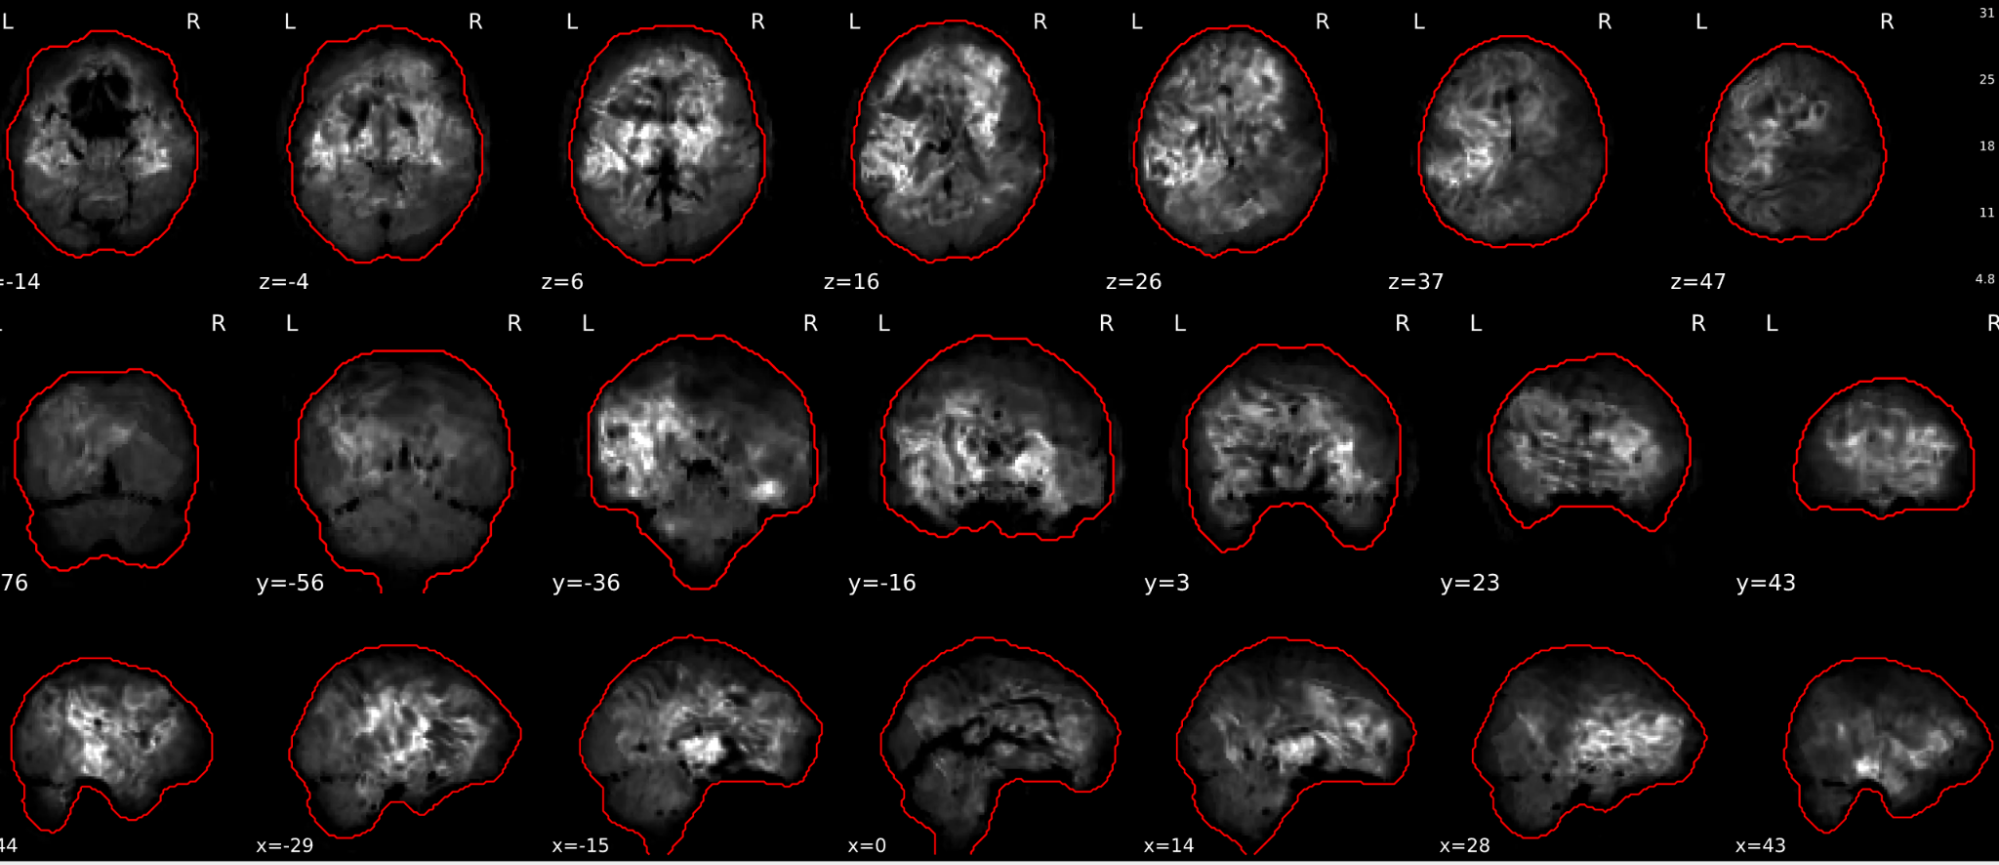

EPI tSNR

In the signal to noise ratio images of the resting state image the desired signal is compared to the amount of background noise. It is important to check all the views (sagittal, coronal, axial) because some artefacts (e.g., stripes) may be evident only in one particular view.

Example of a good subject

- Signal to noise is symmetrically distributed and there is no signal distortion

Example of a bad subject

- Asymmetry

- Potential signal distortion (might represent an artefact)

- Signal drop-out

- Stripes artefact

Clear large artefact (e.g., zebra stripes in example 1) are worth the exclusion of the subject. If you are unsure, check the other quality metrics for that subject to decide whether they should be excluded.

Summary

| good | bad |

|---|---|

| Symmetrical distribution of noise and signal | Asymmetry |

| No disruptions of the signal (no “black patches”) |

Potential signal disruptions (could be related to artefacts) |

| No stripes (sign of high motion) |

Signal drop |

| Stripe artefacts (“zebra” stripes due to motion) |